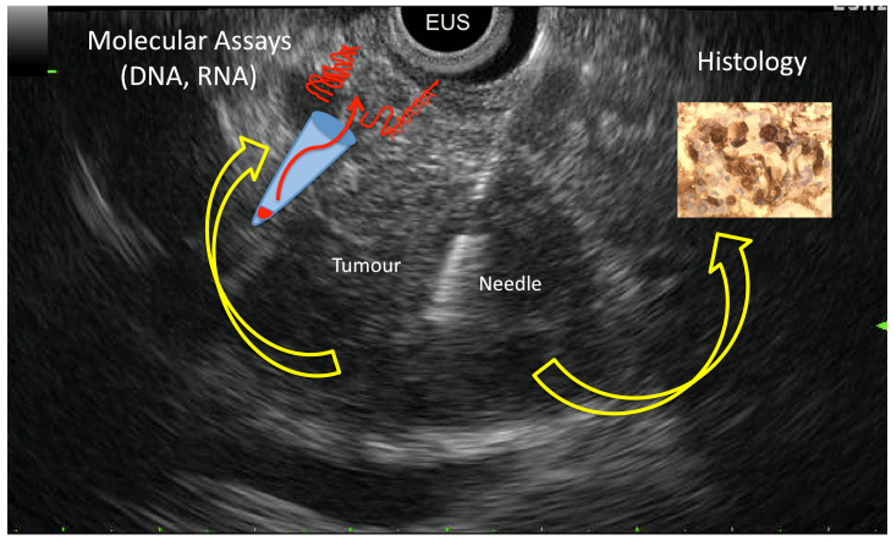

EUS-FNAB is a safe and effective technique for diagnosing PDAC, but its accuracy varies widely. However sampling cytological and histological materials is achieved in 85% of patients with PDAC and permits cytopathological diagnosis. The improvement of molecular biology including DNA and RNA amplification enables the analysis and the quantification of candidate molecular markers in cytological samples collected from EUS-FNAB. Analysis can be performed on cellular material sampled by air blushing or rinsing needle once core biopsy is reclaimed. In this way, the results of molecular analysis can be correlated to histology done on the tissue materials collected during the same needle pass. Thus, molecular analysis of EUS-FNAB material is a complementary tool for the diagnosis of PDAC (Figure 1 shows all possibilities of EUS-FNAB). For this indication, KRAS mutation analysis is highly promising and ready for use at a clinical level. Other molecular markers (including miRNAs) are yet to be characterized. Moreover, EUS-FNAB allows sampling of biological material from patients with locally advanced PDAC that, unfortunately, represent the vast majority of patients diagnosed with this cancer in clinical practice. In this way, cancer scientists have a unique access to tumor material to perform molecular investigations to better understand the physiopathology, the carcinogenesis, and the response to treatment of advanced PDAC.